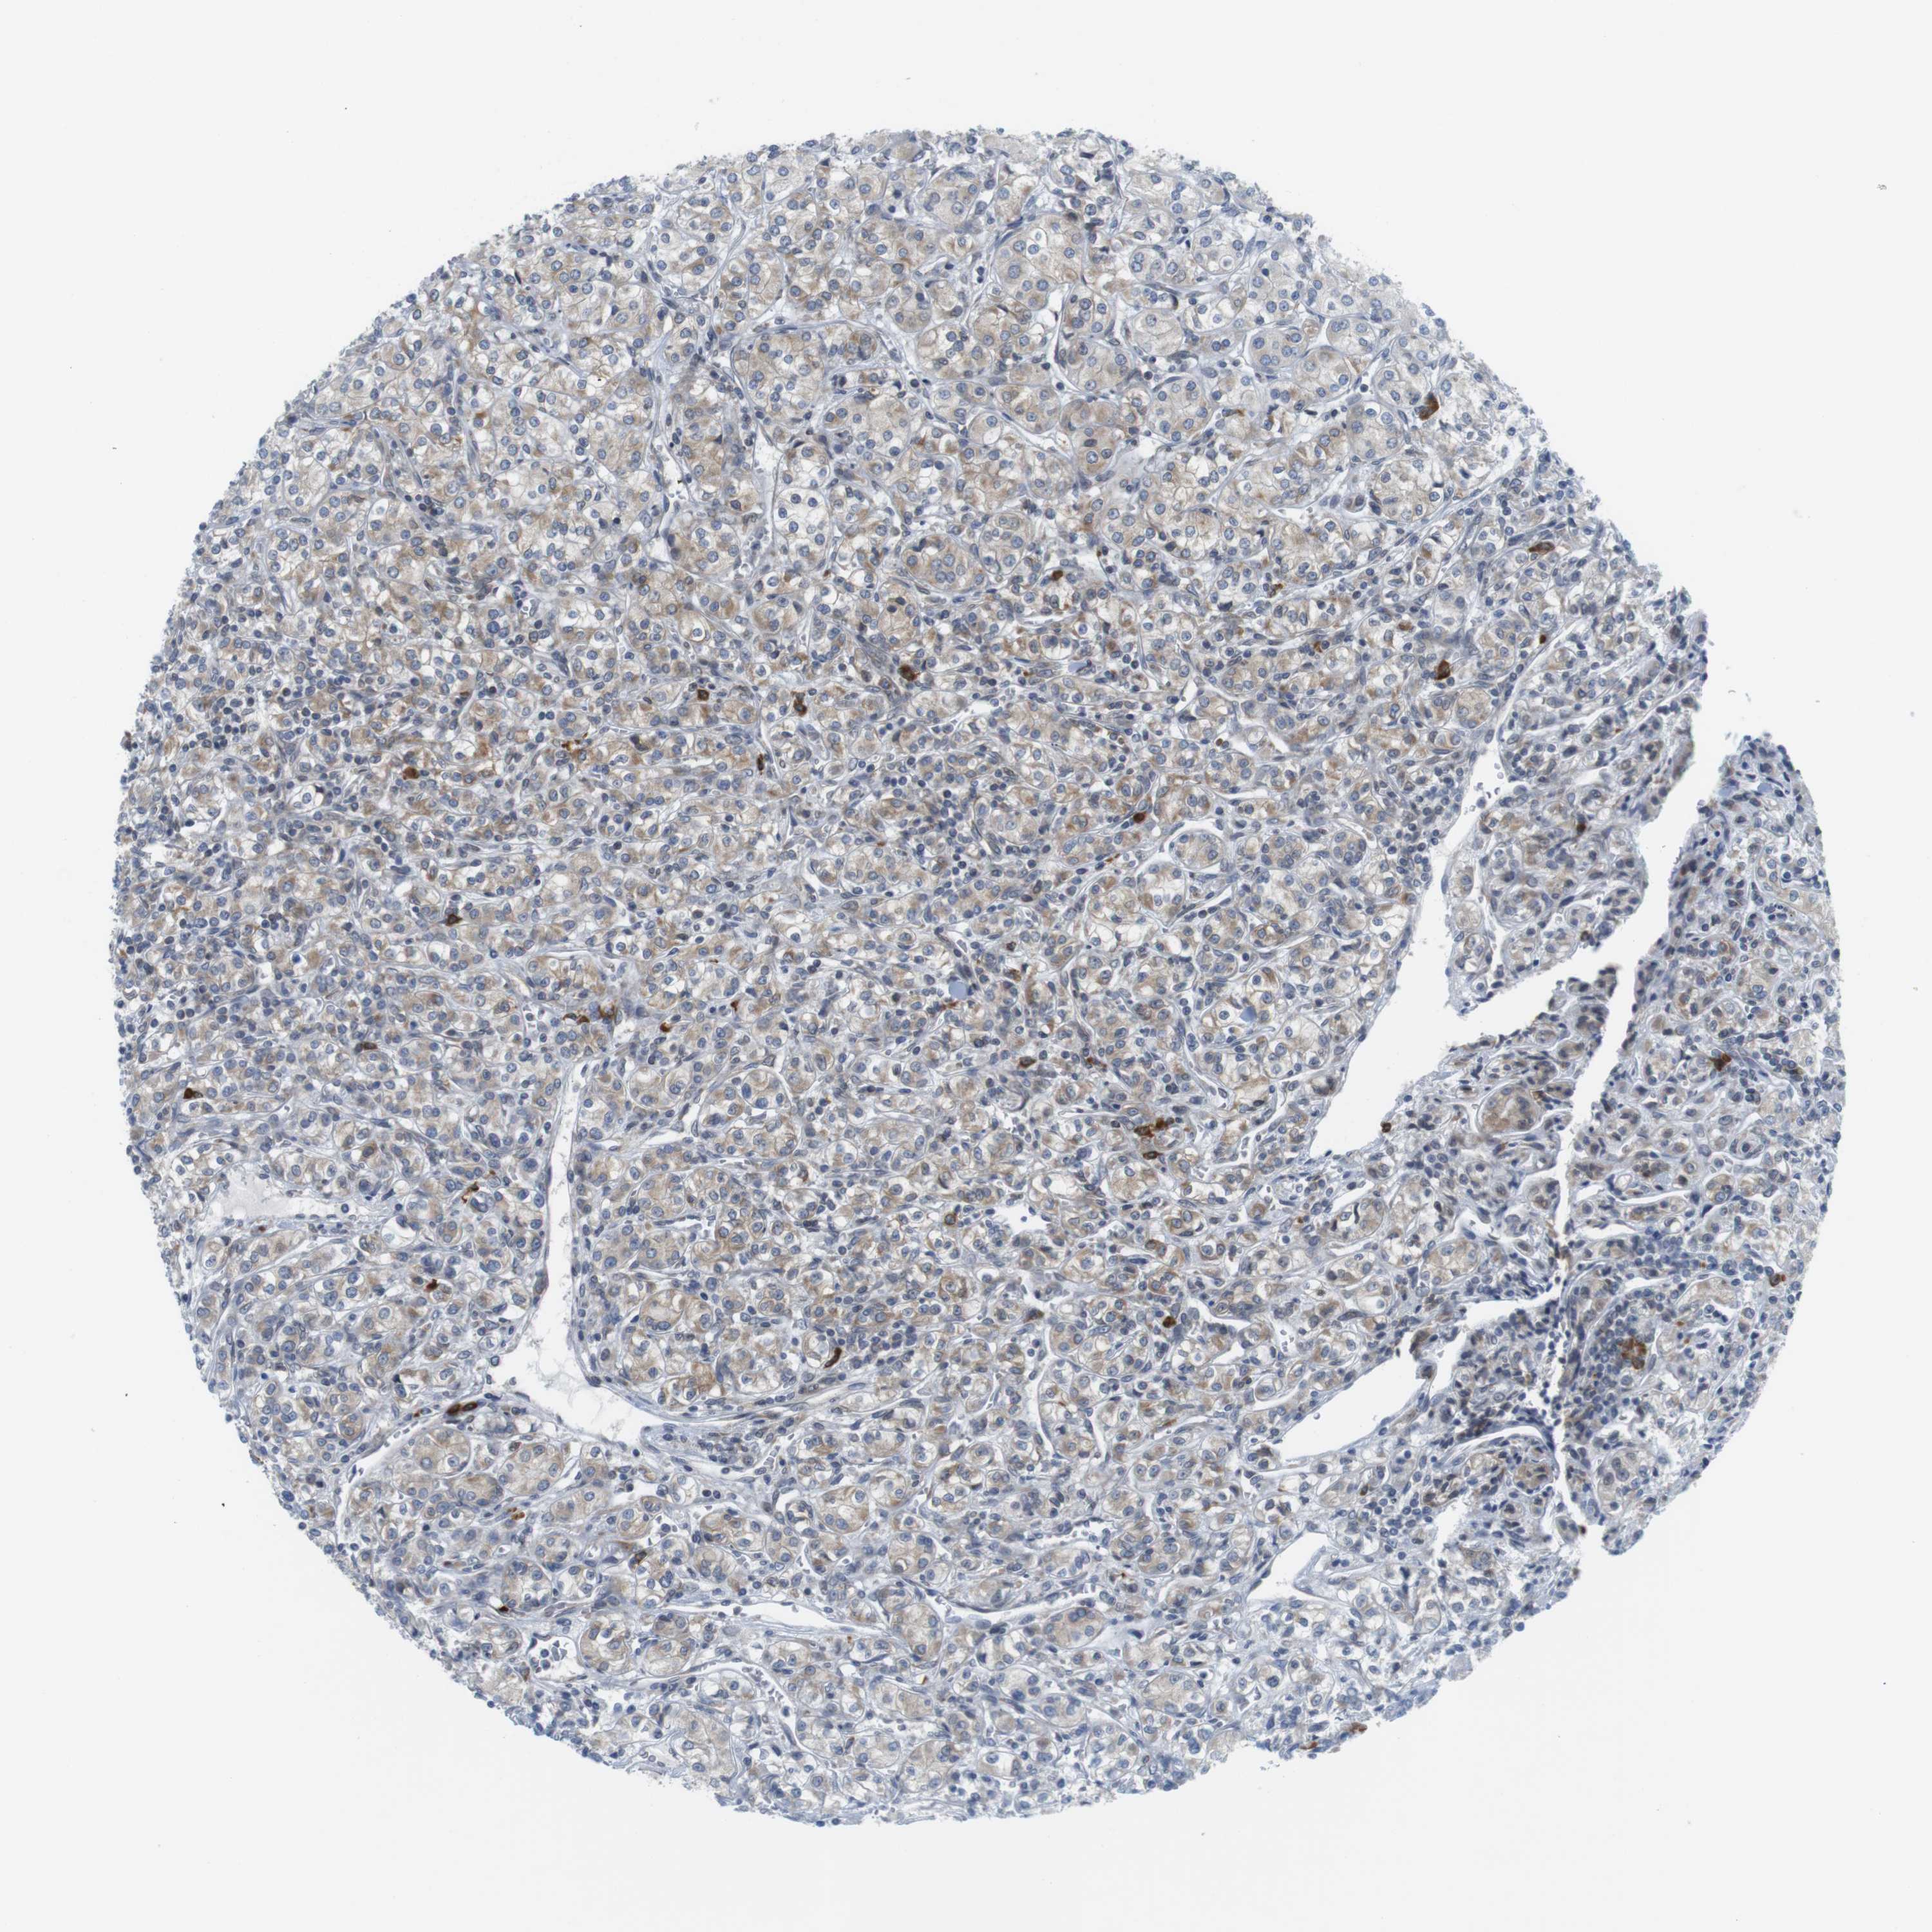

CANCER RENAL CANCER Show tissue menu

KICH TCGA KIRC TCGA KIRC VALIDATION KIRP TCGA PROTEIN RCC CPTAC PROTEIN EXPRESSION